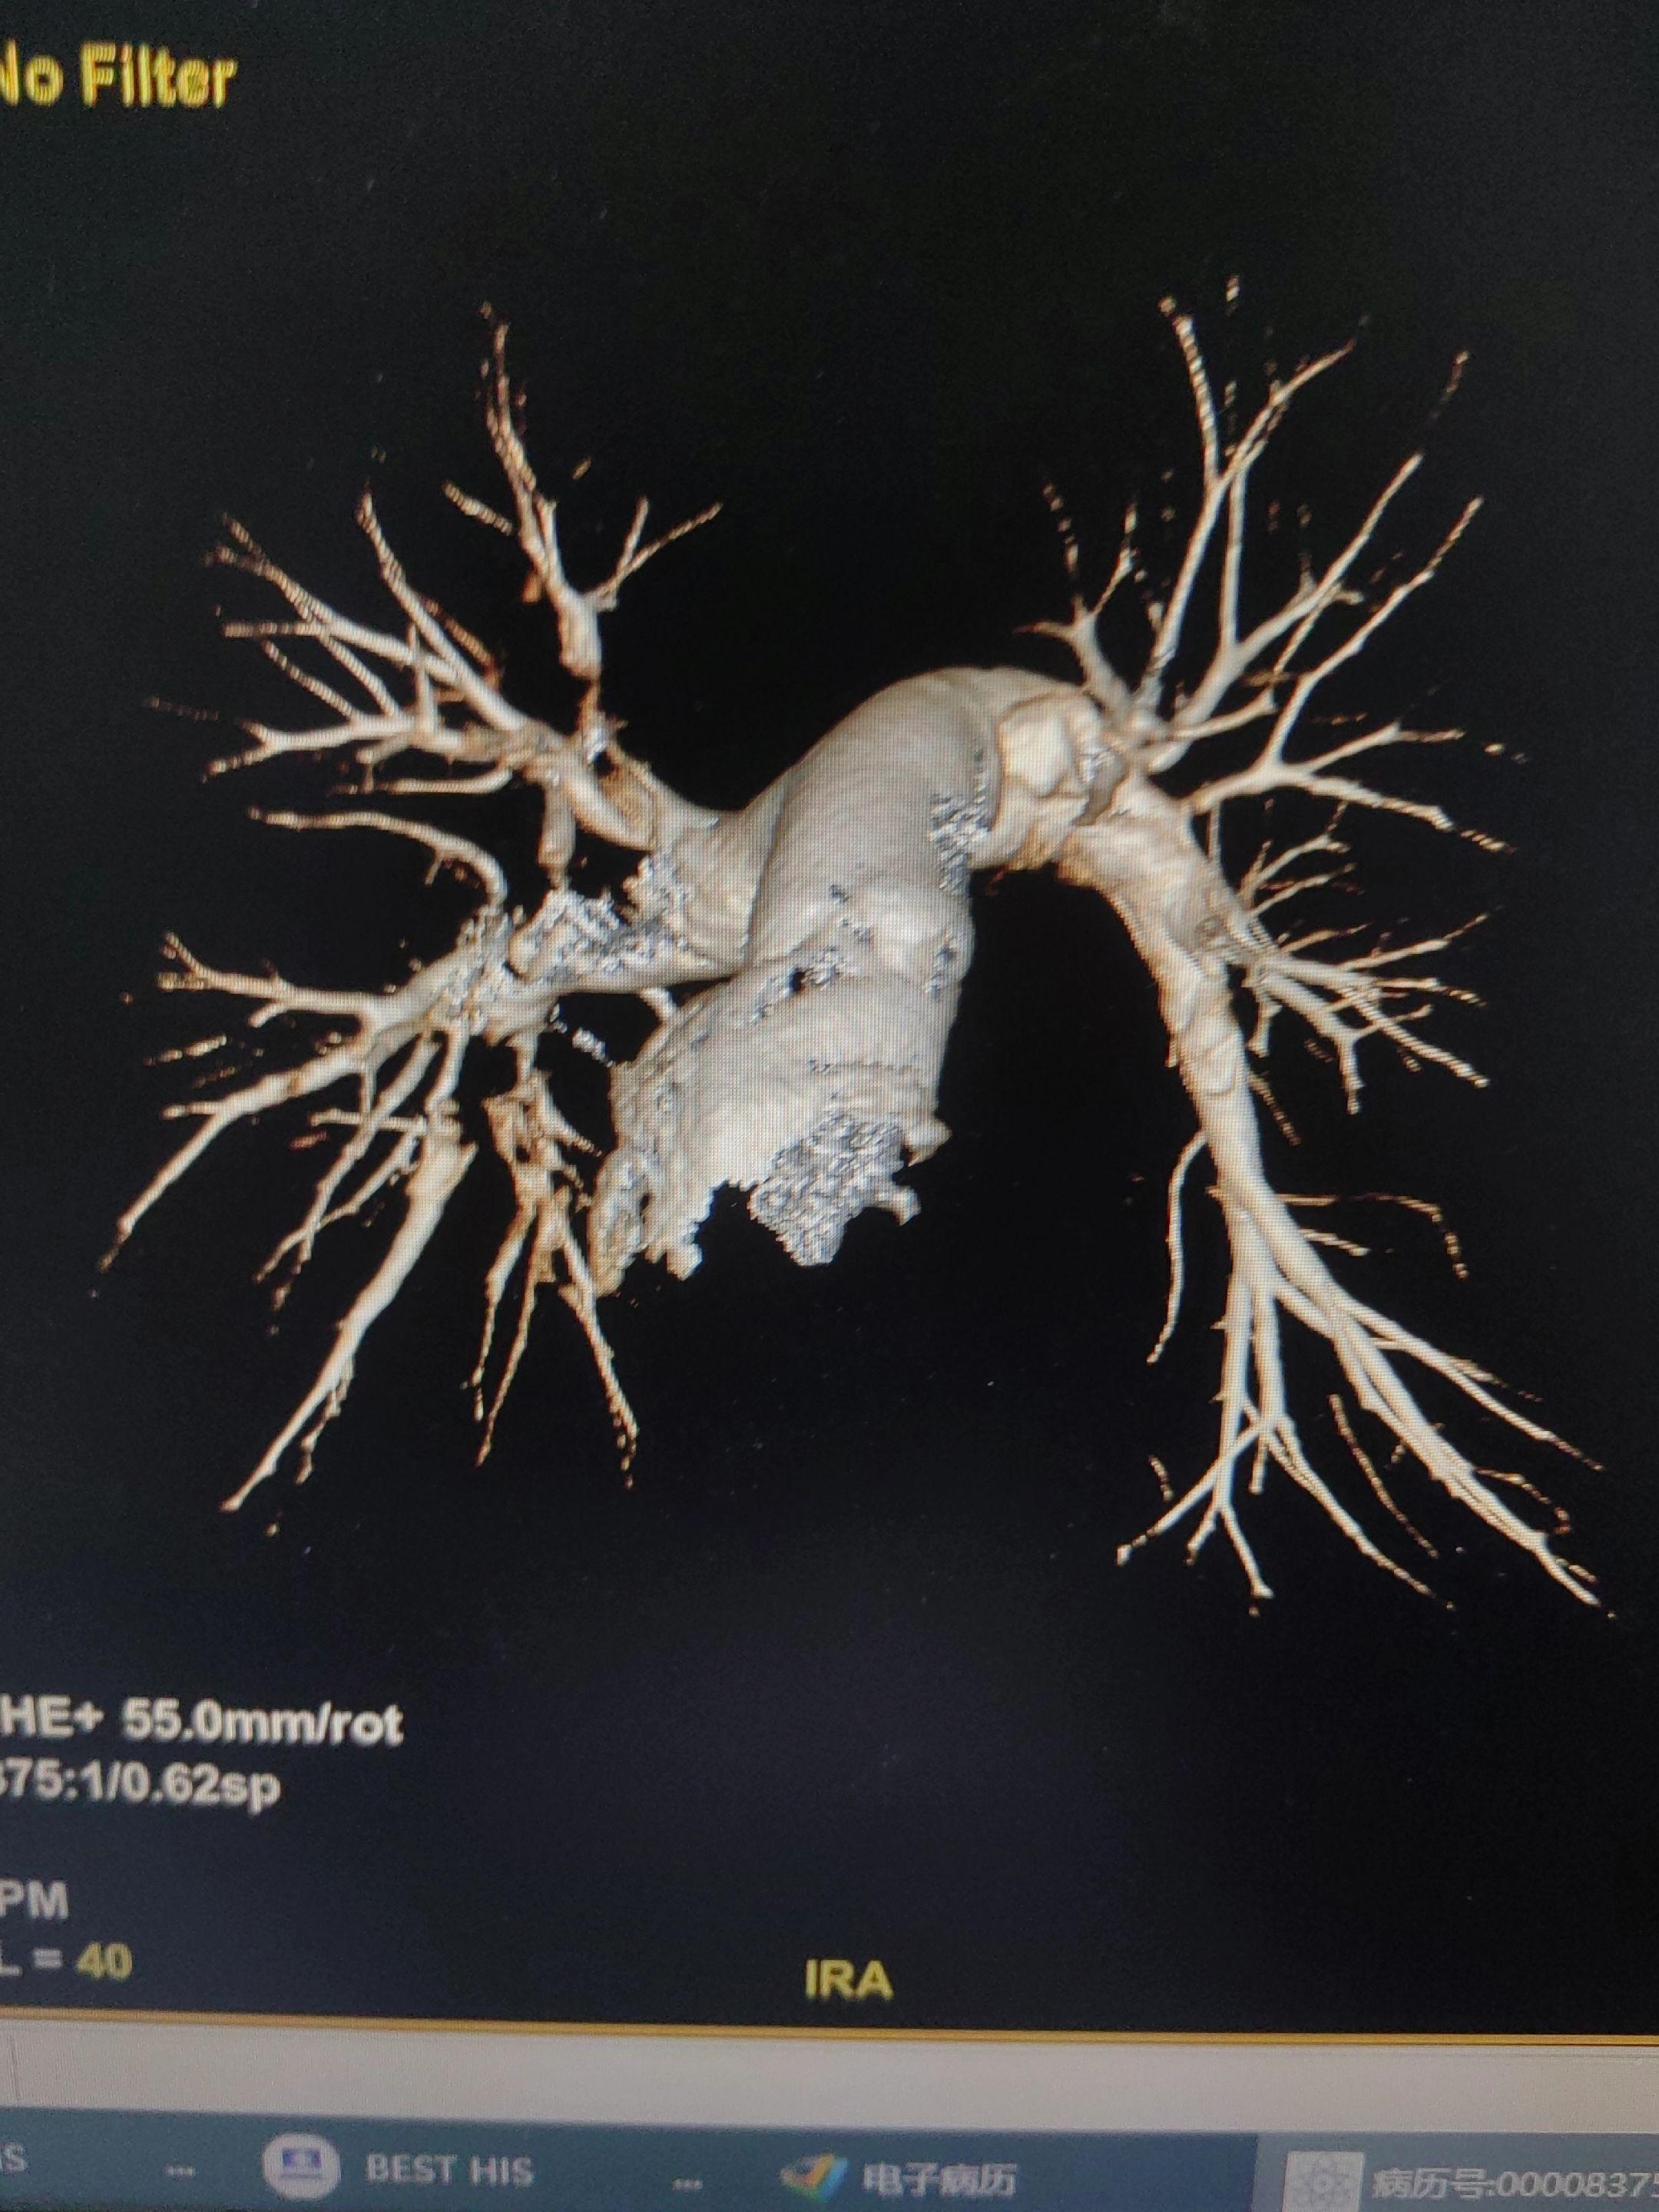

肺栓塞。